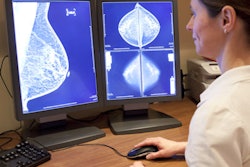

An artificial intelligence (AI) algorithm could triage 20% of screening breast MRI exams as normal without missing any cancers, say researchers from New York City. If used in clinical practice, AI could make breast MRI screening more efficient.

In a presentation from the International Society for Magnetic Resonance in Medicine (ISMRM) meeting in London, researchers from Memorial Sloan Kettering Cancer Center in New York City discussed how they developed a deep-learning model designed to triage normal screening breast MRI exams to a special worklist requiring only abbreviated review by a radiologist.

Breast MRI is used for breast cancer screening in high-risk patients, but more than 98% of these exams are normal. In the study presented at ISMRM 2022, the researchers sought to utilize AI to triage completely normal exams to an abbreviated radiologist worklist; they also compared the algorithm's performance to that of fellowship-trained radiologists. They also wanted to estimate projected time savings from the use of AI.